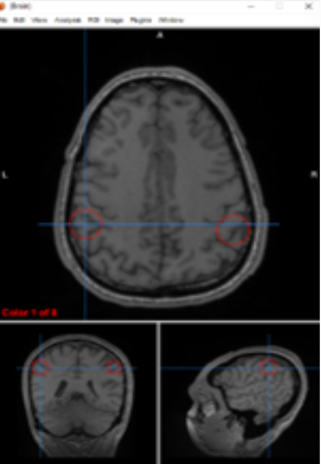

putamen/globus pallidus

regulate voluntary movement, motor planning, and learning

lateral ventricles

circulate and produce cerebrospinal fluid

basal ganglia/thalamus

motor control